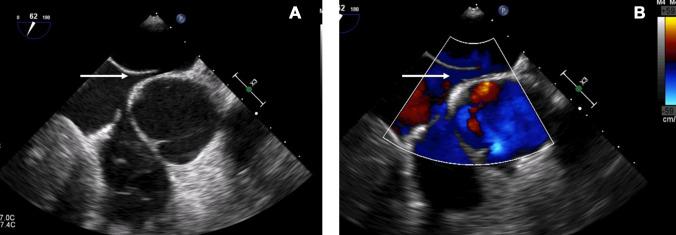

Sickle cell disease (SCD) is an inherited monogenic hemoglobinopathy characterized by formation of sickle erythrocytes under conditions of deoxygenation. Sickle erythrocytes can lead to thrombus formation and vaso-occlusive episodes that may result in hemolytic anemia, pain crisis and multiple organ damage. Moreover, SCD is characterized by endothelial damage, increased inflammatory response, platelet activation and aggravation, and activation of both the intrinsic and the extrinsic coagulation pathways. Cerebrovascular events constitute an important clinical complication of SCD. Children with SCD have a 300-fold higher risk of acute stroke and by the age of 45 about 25% of patients have suffered an overt stoke. Management and prevention of stroke in patients with SCD is not well defined. Moreover, the presence of patent foramen ovale (PFO) increases the risk of the occurrence of an embolic cerebrovascular event. The role of PFO closure and antiplatelet or anticoagulation therapy has not been well investigated. Moreover, during COVID-19 pandemic and taking into account the increased rates of thrombotic events and the difficulties in blood transfusion, management of SCD patients is even more challenging and difficult, since data are scarce regarding stroke occurrence and management in this specific population in the COVID-19 era. This review focuses on pathophysiology of stroke in patients with SCD and possible treatment strategies in the presence of PFO.

镰状细胞病(SCD)是一种遗传性单基因血红蛋白病,其特征是在缺氧条件下形成镰状红细胞。镰状红细胞可导致血栓形成和血管阻塞发作,从而导致溶血性贫血、疼痛危象和多器官损伤。此外,SCD 的特征还包括内皮损伤、炎症反应增加、血小板激活和加重,以及内源性和外源性凝血途径的激活。脑血管事件是 SCD 的一个重要临床并发症。患有 SCD 的儿童发生急性中风的风险高 300 倍,到 45 岁时,约有 25%的患者发生过明显中风。SCD 患者中风的管理和预防尚未得到很好的定义。此外,卵圆孔未闭(PFO)的存在会增加发生栓塞性脑血管事件的风险。PFO 闭合和抗血小板或抗凝治疗的作用尚未得到很好的研究。此外,在 COVID-19 大流行期间,考虑到血栓形成事件的发生率增加以及输血困难,SCD 患者的管理更加具有挑战性和困难,因为在 COVID-19 时代,针对该特定人群中风发生和管理的数据很少。本文重点介绍 SCD 患者中风的病理生理学以及 PFO 存在时的可能治疗策略。